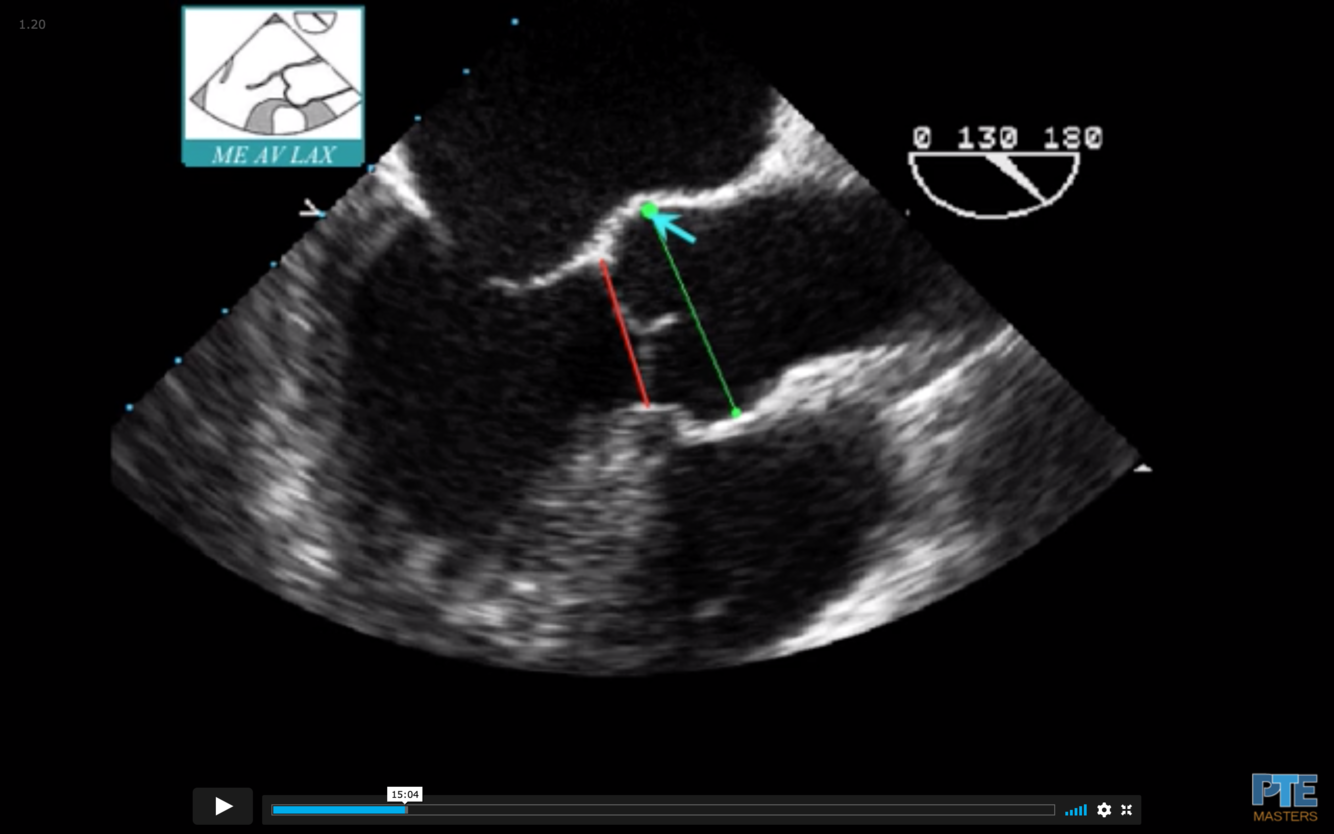

What is the measurement seen here?

Sinus of Valsalva

What is the blue arrow indicating?

Sinotubular Ridge or Sinuotubular Junction

What is seen in red?

Aortic Annulus

What is the normal size of the Aortic Root in an adult?

What measurement is termed dilated?

Normal = < 40 mm (4.0 cm)

Dilated = >40 mm